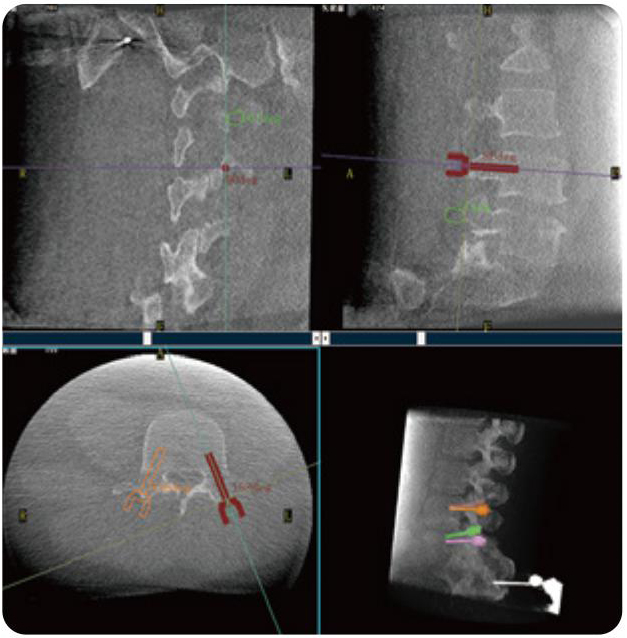

PL300B可應(yīng)用于多節(jié)段脊柱外科手術(shù),輔助醫(yī)生定位病灶部位,為脊柱外科手術(shù)(經(jīng)皮椎體成形術(shù)、椎弓根螺釘內(nèi)固定術(shù)等術(shù)式)提供術(shù)前手術(shù)流程規(guī)劃、入釘位置、角度可視化引導(dǎo),模擬仿真入釘輔助。

PL300B搭配普愛醫(yī)療自主研發(fā)生產(chǎn)的平板3D C形臂,借助一體化自適應(yīng)配準(zhǔn)( 軌跡配準(zhǔn))技術(shù),通過追蹤C形臂三維采集軌跡,自動完成圖像坐標(biāo)建立和系統(tǒng)坐標(biāo)配準(zhǔn)。配準(zhǔn)精度更高,操作步驟少,系統(tǒng)運作效率高。